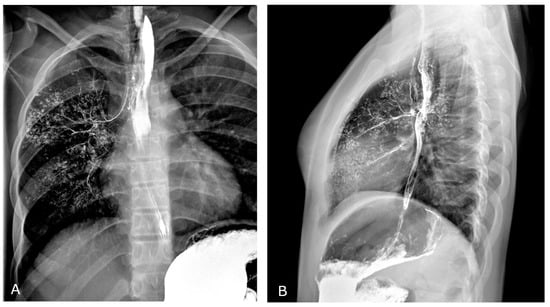

Multi-Contrast Differentiation by Dual-Energy Spectral CT Angiography in a Patient with Pulmonary Barium Granulomas

2. Case Report